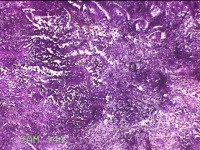

宫颈内容物

性别

女

年龄

29岁

临床诊断

异常子宫出血

一般病史

不规则阴道流血1个月余。

标本名称

大体所见

灰白暗红色不规则碎组织1.8x1.3x0.3cm一堆。

图4